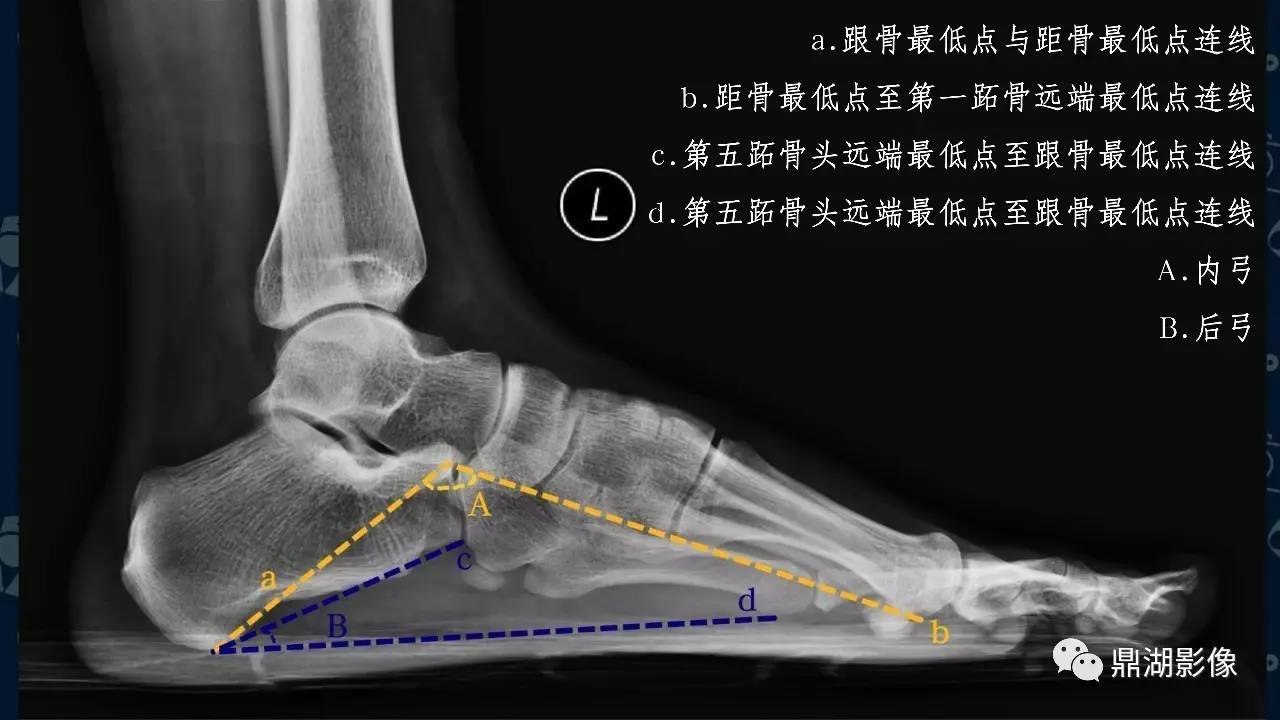

扁平足(平足)指的是正常足弓的缺失,或称为足弓塌陷。值得注意的是,平足不等于平足症,也不是所有的平足都需要治疗。如果平足者合并有疼痛等症状时,就被称为平足症,才可能需要治疗。